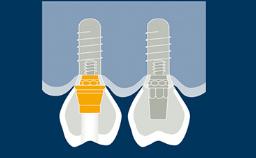

O clínico que pratica implantodontia é confrontado com diferentes situações clínicas, que variam de um único dente ausente, a um espaço edêntulo com vários dentes ausentes até completar rebordos totalmente edêntulos. Uma vez estabelecido um plano de tratamento completo, diferentes desenhos de configurações podem ser possíveis para próteses implantossuportadas. Cada desenho da prótese tem suas vantagens e desvantagens. O desenho da prótese deve basear-se na condição clínica para garantir que o número apropriado de implantes seja instalado nas posições protéticas corretas usando implantes com dimensões apropriadas.

- espaços dentais unitários

- espaços edêntulos curtos